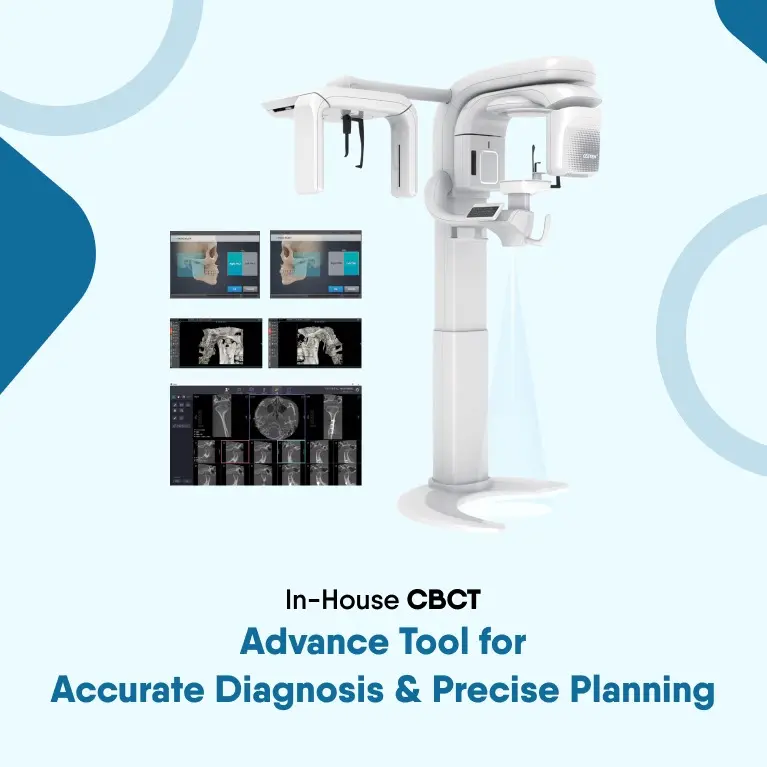

Full Mouth X-RAY

We provide full mouth X-rays for accurate diagnosis, carefully designed for your comfort, delivering fast and precise results.

3D Dental Scan

We offer 3D dental scans, ensuring detailed imaging for advanced treatment, providing fast and accurate results throughout your visit.